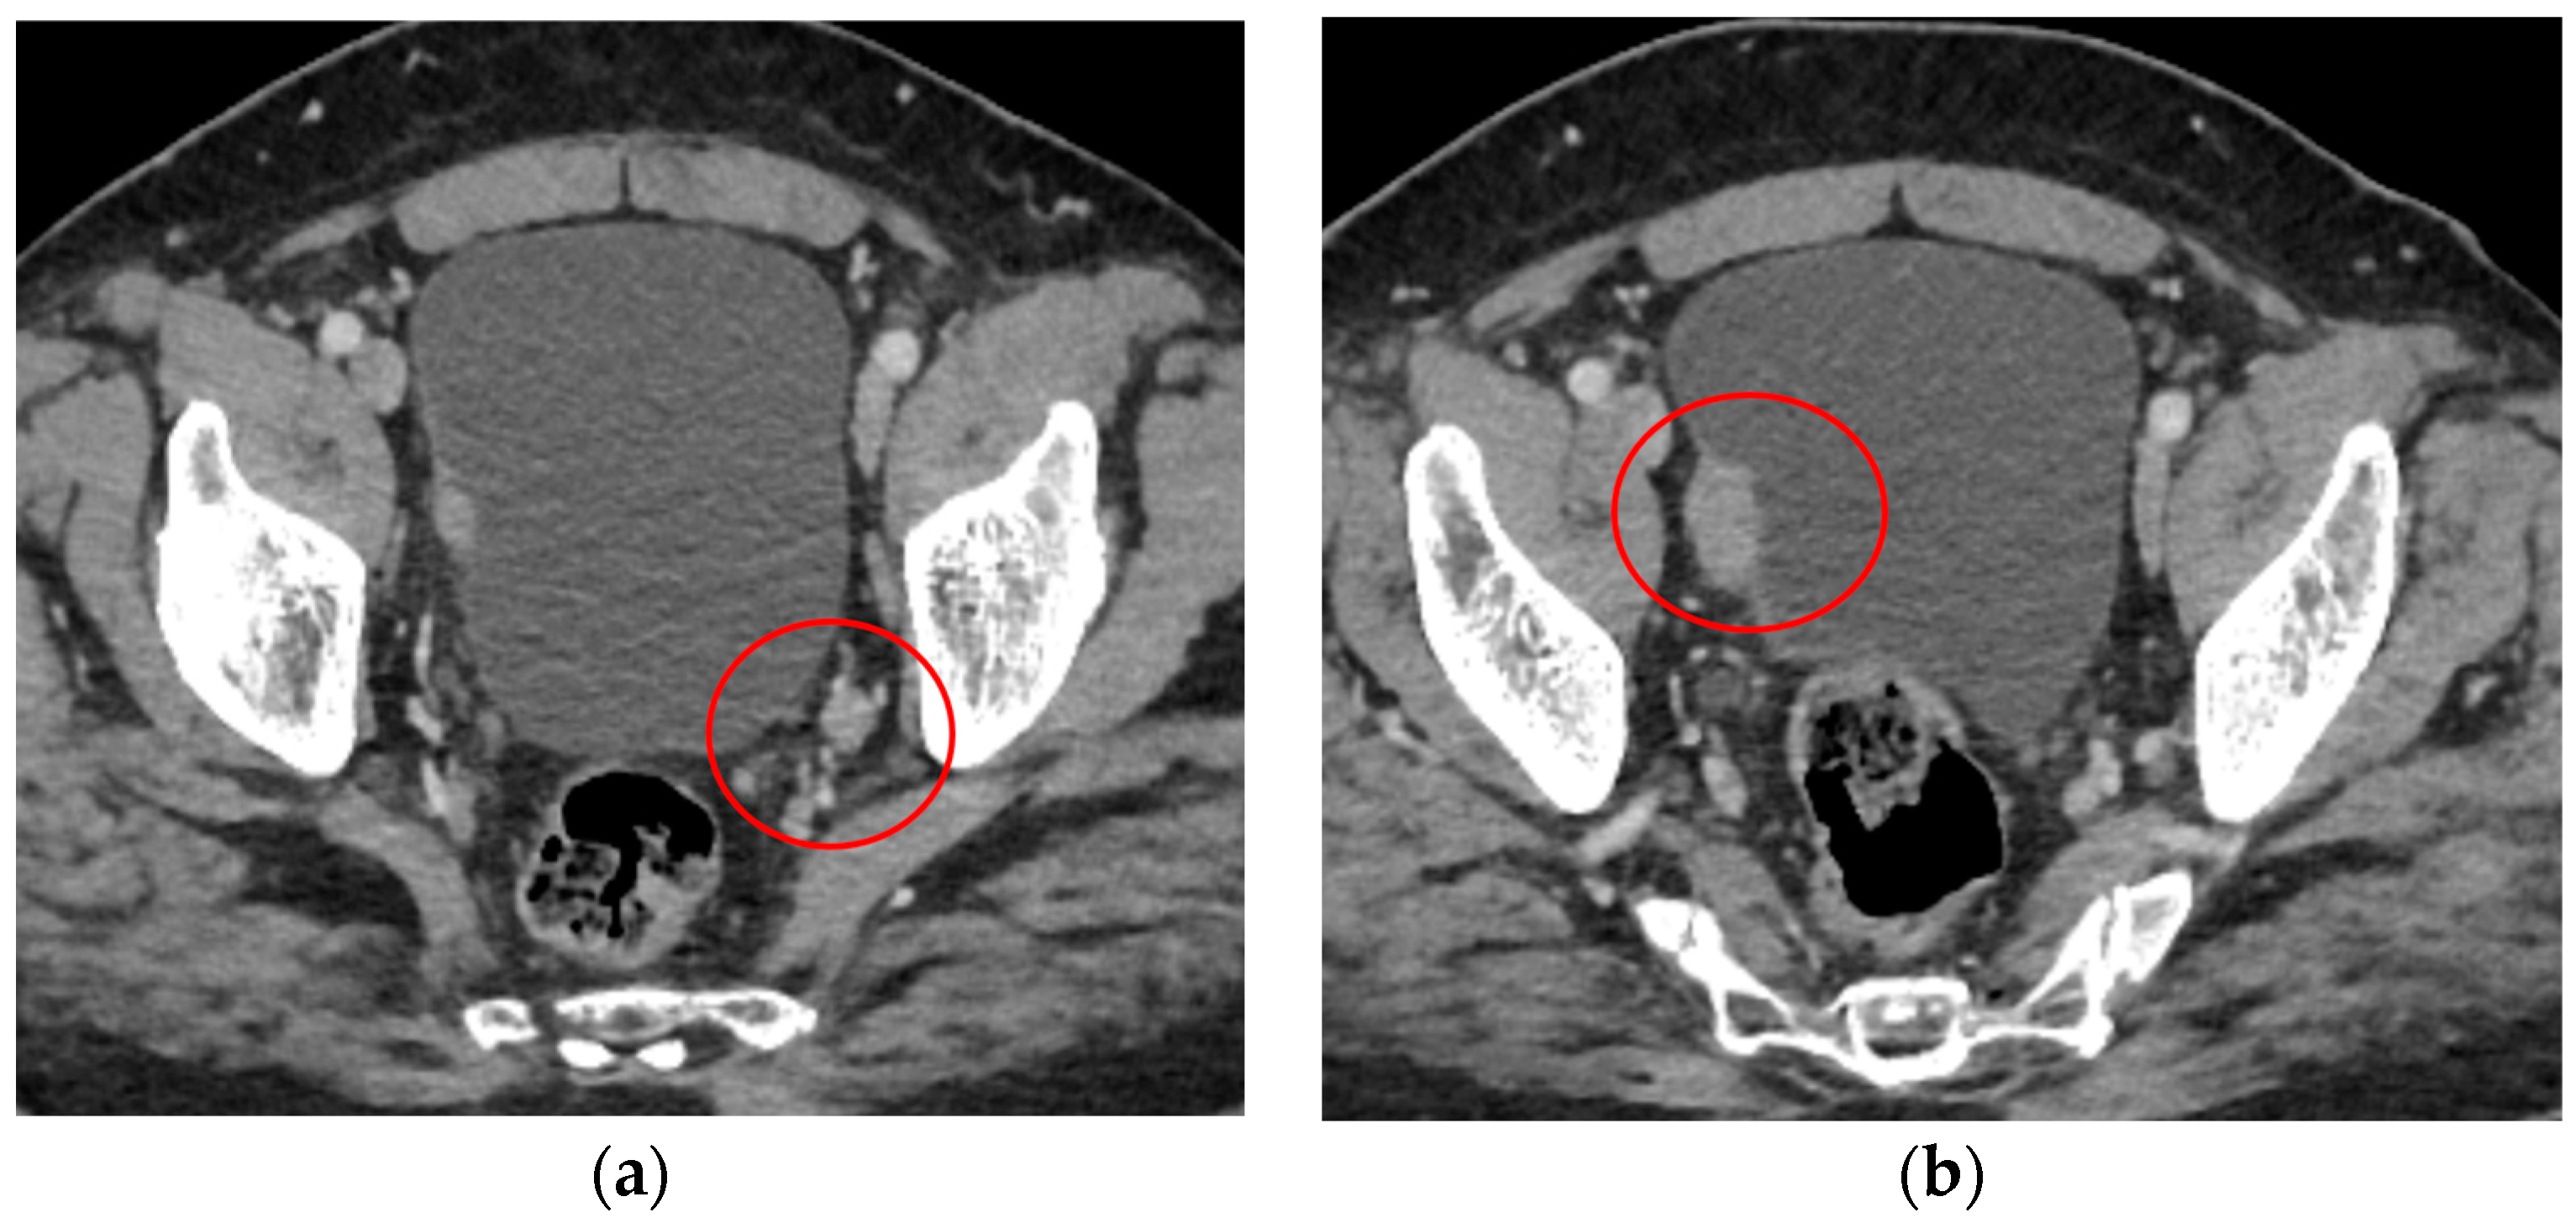

2. Case Report